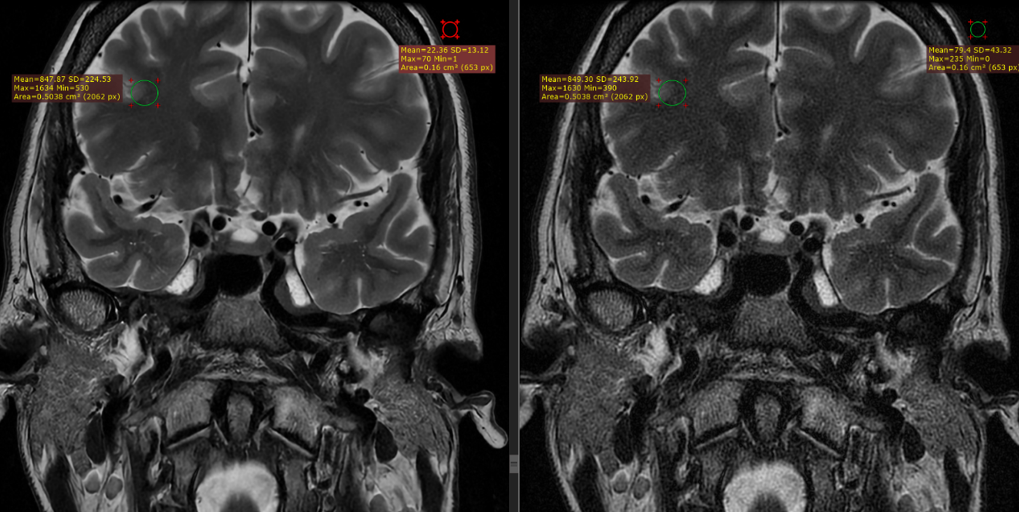

Figure 1 displays representative brain images of a thin-slice coronal T2 weighted fast spin echo pulse sequence, which was acquired with a small field of view of 14 cm. The image quality improved with DL-based reconstruction, and upon signal measurements, a 354% increase in SNR was noted.

![[Uncaptioned image]](/html/2206.01082/assets/Figure_1.png)

Figure 1. 2 mm coronal T2 weighted fast spin echo pulse sequence, with a small field of view of 14 cm. SNR gains of 354% were noted when the image was reconstructed through the DL-based reconstruction pipeline (left) compared to the conventional pipeline (right).